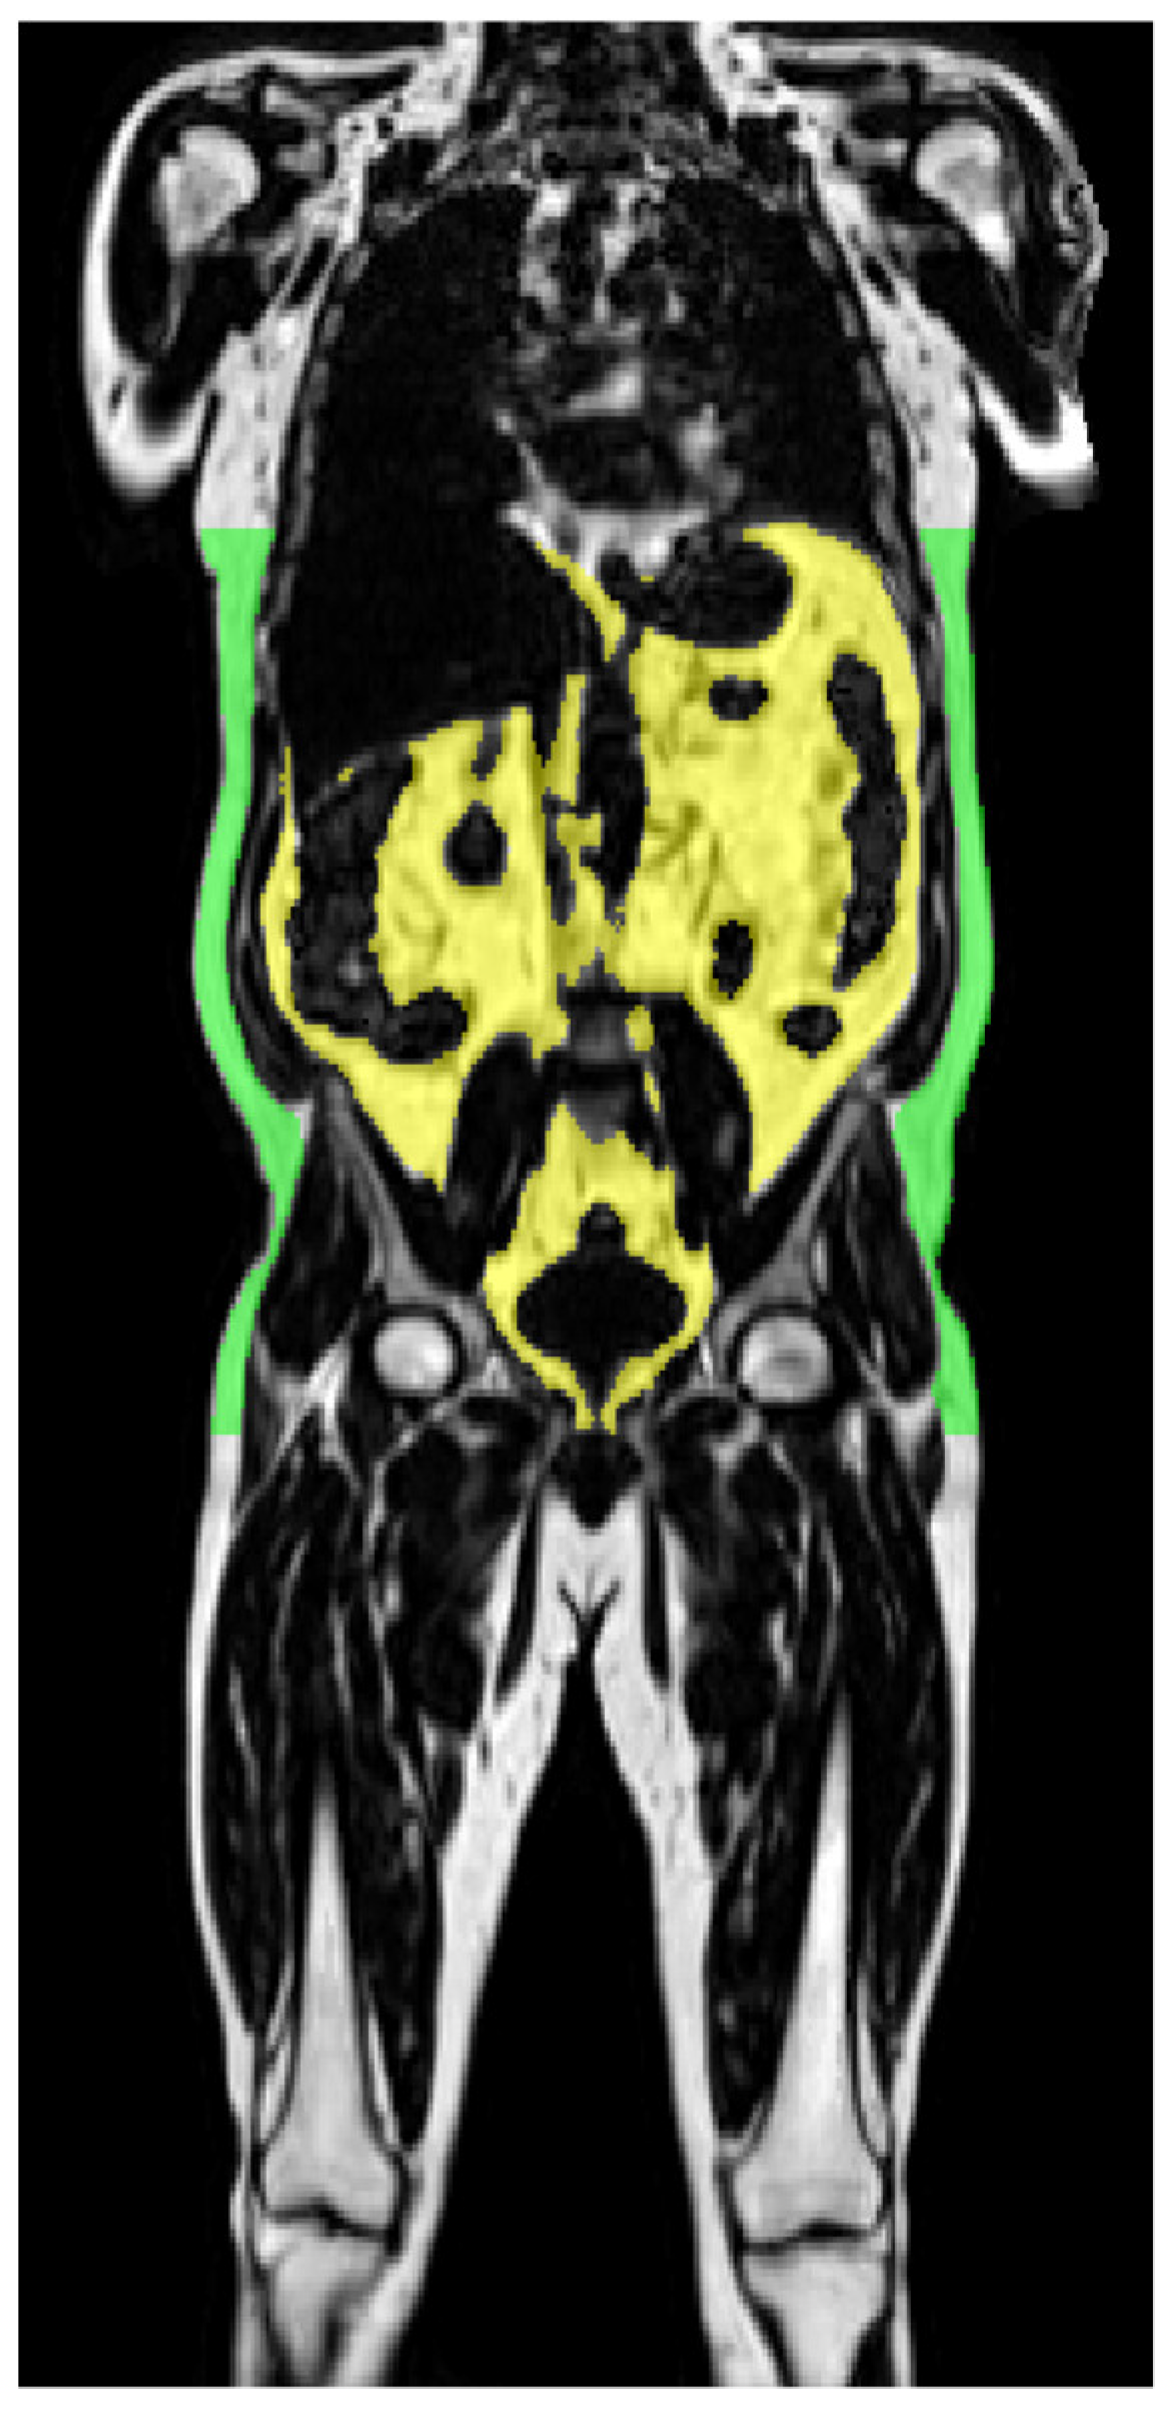

2.1. Magnetic Resonance Imaging